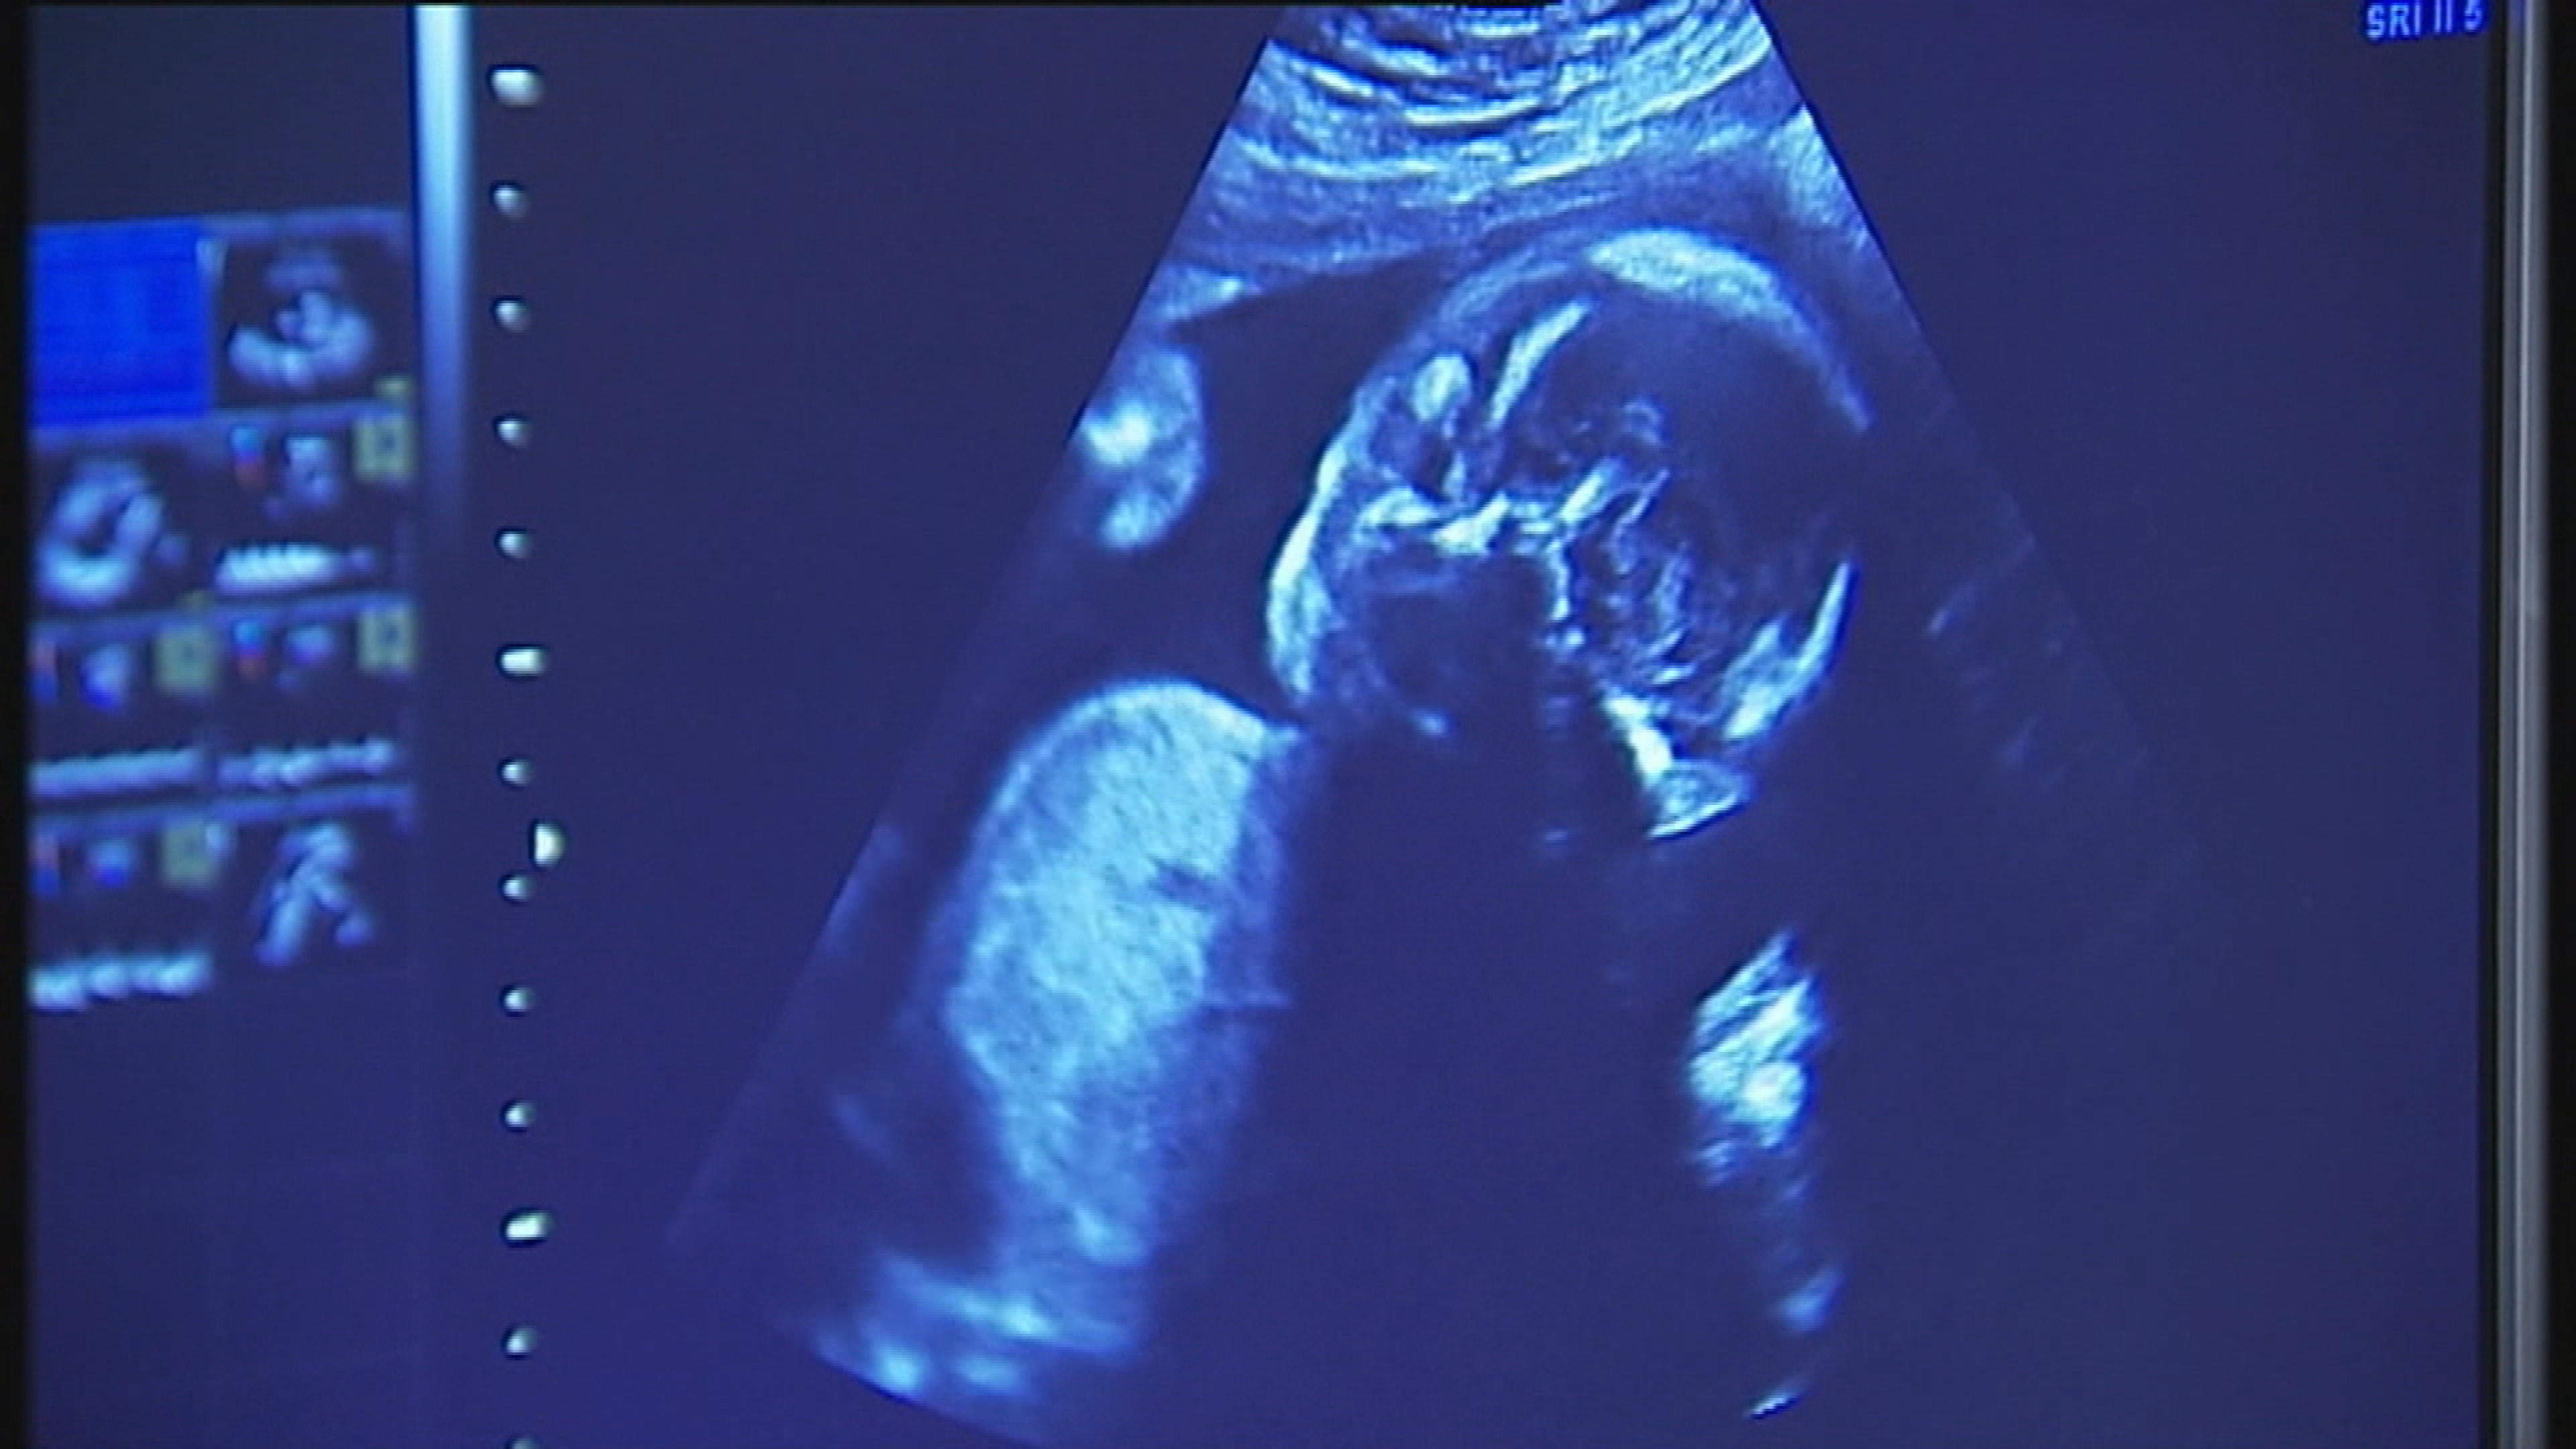

Woman trying for baby prescribed wrong drugs that can cause miscarriage

Charlotte Riley was treated by Jersey's Rheumatology Department for rheumatoid arthritis, now she says medics are not even sure that was the correct diagnosis.